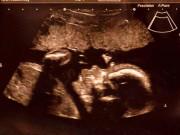

Các bác sĩ tiến hành khám lâm sàng và kết luận thể trạng bệnh nhân mệt mỏi, da niêm mạc nhợt, thai 23 tuần, có khối u đại tràng kích thước gần 8 cm gây tắc ruột.

Chị T. được phát hiện ung thư đại tràng khi đang mang bầu 23 tuần.

Qua hội chẩn chuyên khoa, các bác sĩ chẩn đoán chị T. mắc ung thư đại tràng góc gan, thai 23 tuần. Thông tin này khiến chính sản phụ và người nhà vô cùng đau đớn. Sau đó chị được chỉ định phẫu thuật cấp cứu cắt khối u đại tràng đồng thời bảo tồn thai. Kíp phẫu thuật do bác sĩ Nguyễn Quốc Hùng, bác sĩ Hoàng Văn Quỳnh cùng các kỹ thuật viên thực hiện.